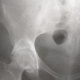

Ж.33 года .На оформление группы.Связывает начало после эпидур.анестезии 3 года назад .Архив просила принести.В таком возрасте вижу впервые такие изменения.Что с сакральным справа. Как бы звучало ваше заключение?Асептический некроз  головки справа есть?МРТ нужно?Спасибо.

АНГБК+Сакроилеит

Покажите признаки АНГБК

Первой мыслью было АНГБ, но...Отмечается неровность контура не только головки бедра, но и суставной впадины. Головка неравномерно порозна. Думаю артрИТ тазобедренного сустава - более вероятно.Если есть возможность выыполнить МРТ, было бы замечательно.

Сделайте нормальные снимки илеосакральных. Потом поговорим. Насчёт ТБС согласен с Натальей

АНГБ, 2 стадия. ДОА сустава.